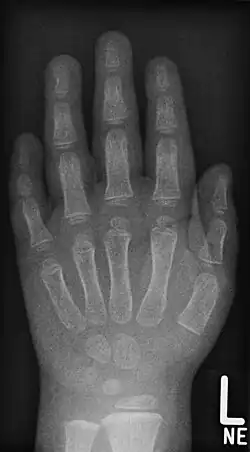

Brachyphalangia

Brachyphalangia to wada wrodzona polegająca na skróceniu kości tworzących dłoń. W zależności od tego, która kość uległa skróceniu, używa się następujących terminów:

- brachytelephalangia – skrócenie paliczków dystalnych (dalszych; odsiebnych)

- brachymesophalangia – skrócenie paliczków środkowych

- brachybasophalangia – skrócenie paliczków proksymalnych (bliższych; dosiebnych)

- brachymetacarpia – skrócenie kości śródręcza

- brachymetatarsia – skrócenie kości śródstopia.